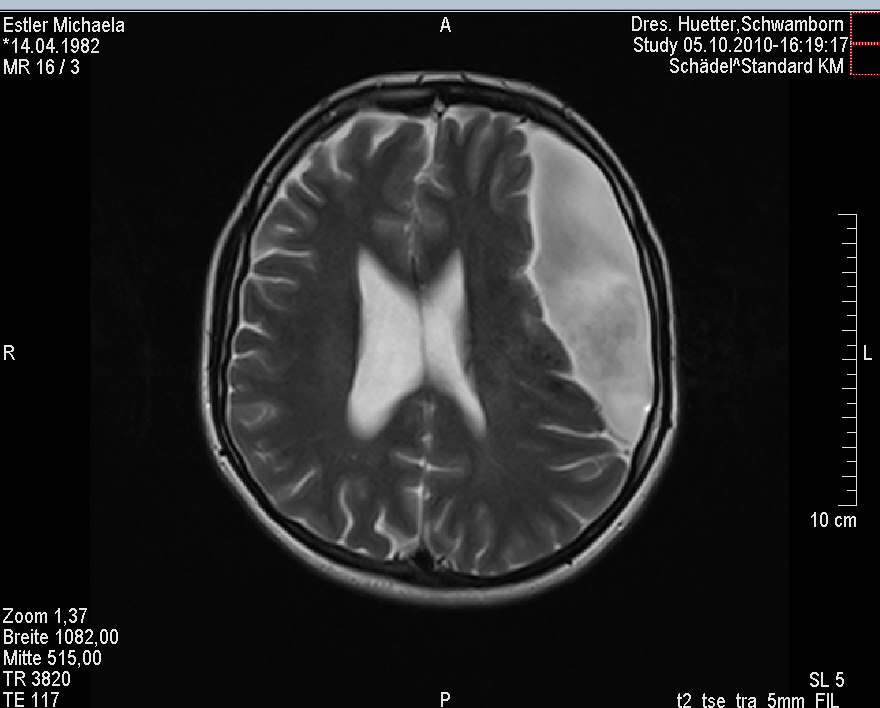

Ich stell euch hier noch eine kleine Galerie rein mit den neuesten Bildern. Ich denke es ist unübersehbar, dass das Ding gewachsen ist, außerdem mir meine komplette Hirnmittelline verschiebt und immer mehr Rücklagerung bekommt und Richtung Hirnsteuerungszentrum drückt. Meine häufiger auftretenden Stürze und Koordinationsprobleme werden also in naher Zukunft sicherlich nicht weniger werden und mein Doc und ich werden uns wohl auch zeitnah über eine weitere Klinik und eine mögliche weitere OP unterhalten müssen.